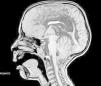

Resonancia nuclear magnética craneoespinal: corte sagital que muestra malformación de Arnold-Chiari tipo II con hipogenesia del cuerpo calloso y quiste interhemisférico asociado. Hipogenesia del vermis cerebeloso, válvula de derivación ventricular con ventrículos colapsados, lesión porencefálica temporooccipital izquierda, múltiples anomalías del desarrollo cortical consistentes en múltiples heterotopias subependimarias y subcorticales y posible polimicrogiria frontal.